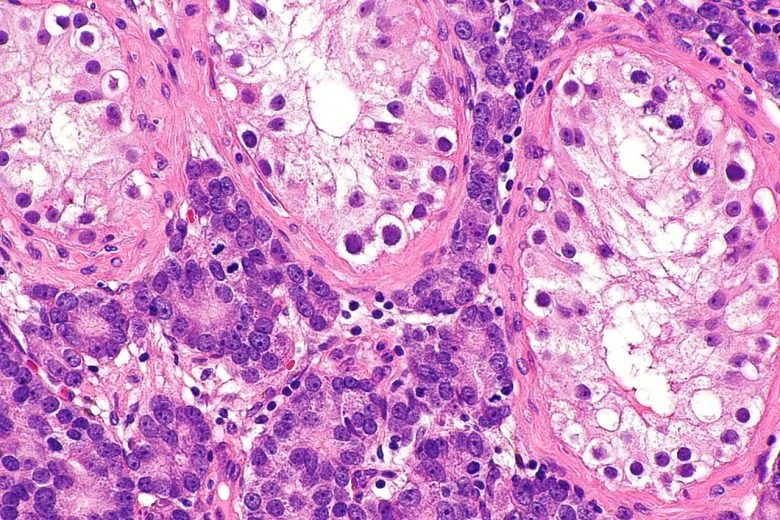

Pancreatic cancer

“Pancreatic cancer can develop from two kinds of cells in the pancreas: exocrine cells and neuroendocrine cells, such as islet cells. The exocrine type is more common and is usually found at an advanced stage. Pancreatic neuroendocrine tumors (islet cell tumors) are less common but have a better prognosis.”

Image Credit: Nephron / Wikimedia Commons.